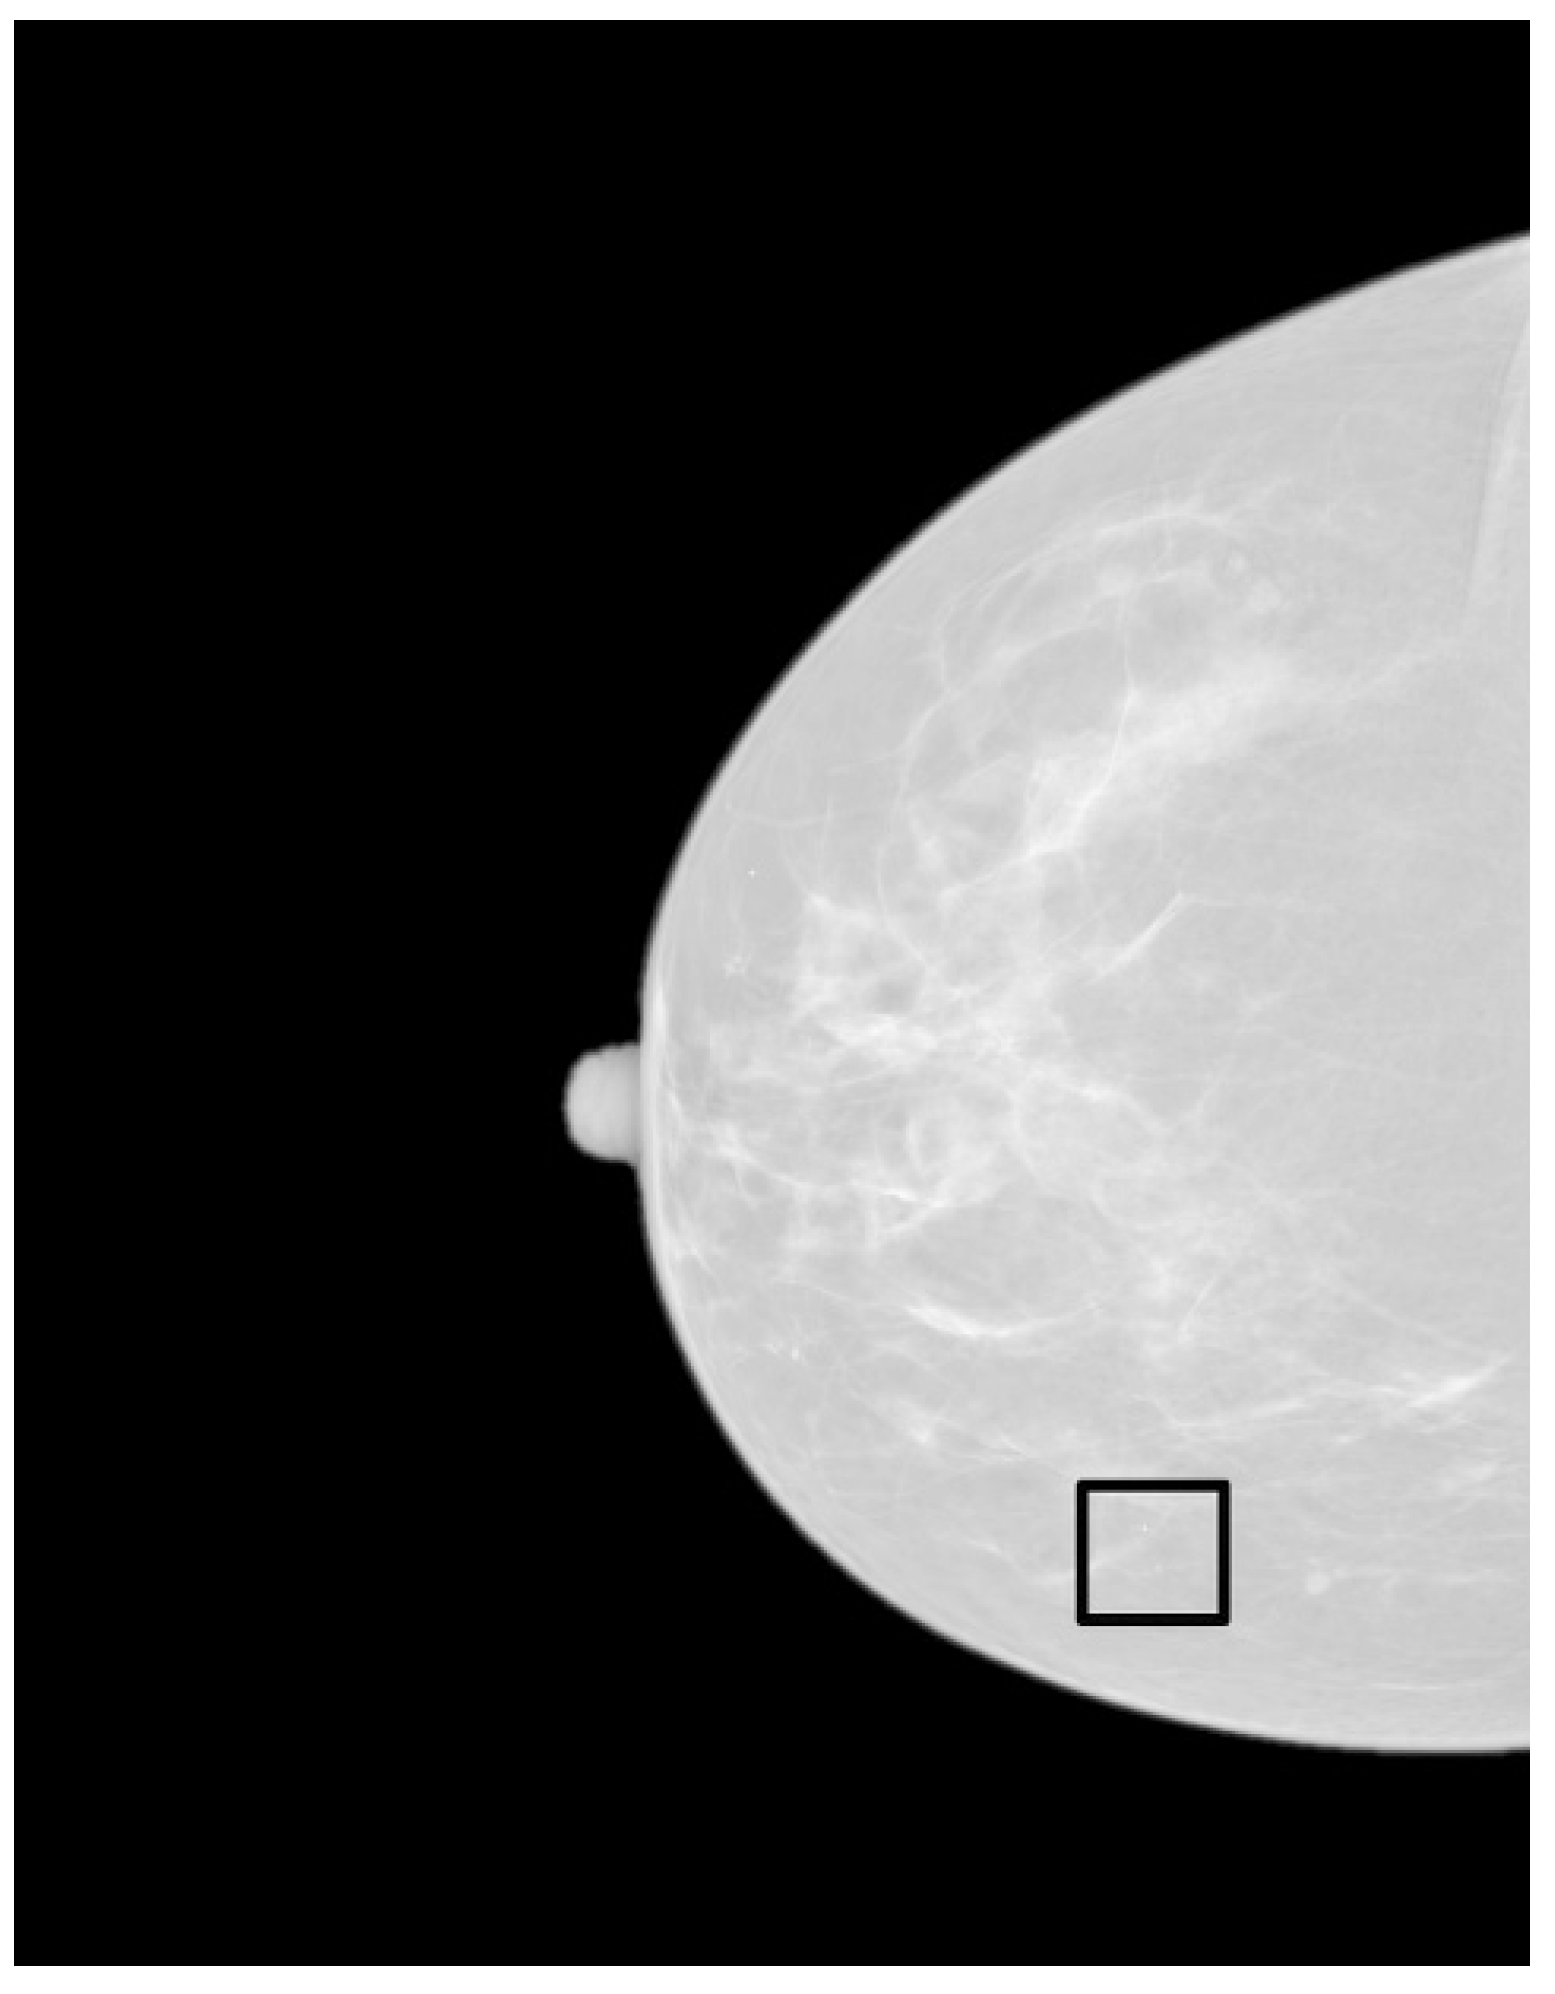

- Zoom the region of interest of the image around the microcalcification clusters. Use simple nearest neighbor zooming without interpolation.

- Use a complete set of fractal filters for pixel diffusion. Convolve each fractal mask with the original ROI. A very good zooming factor is × 8 when a set of fractal masks composed of 5 × 5 pixels is used, with angular increments of 45 degrees from 0 to 315 degrees.